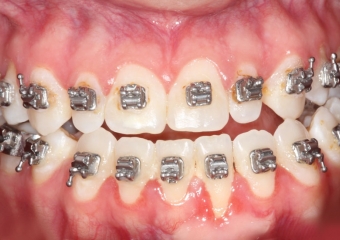

Mordida inicial - Clínica Cliniface

Mordida inicial